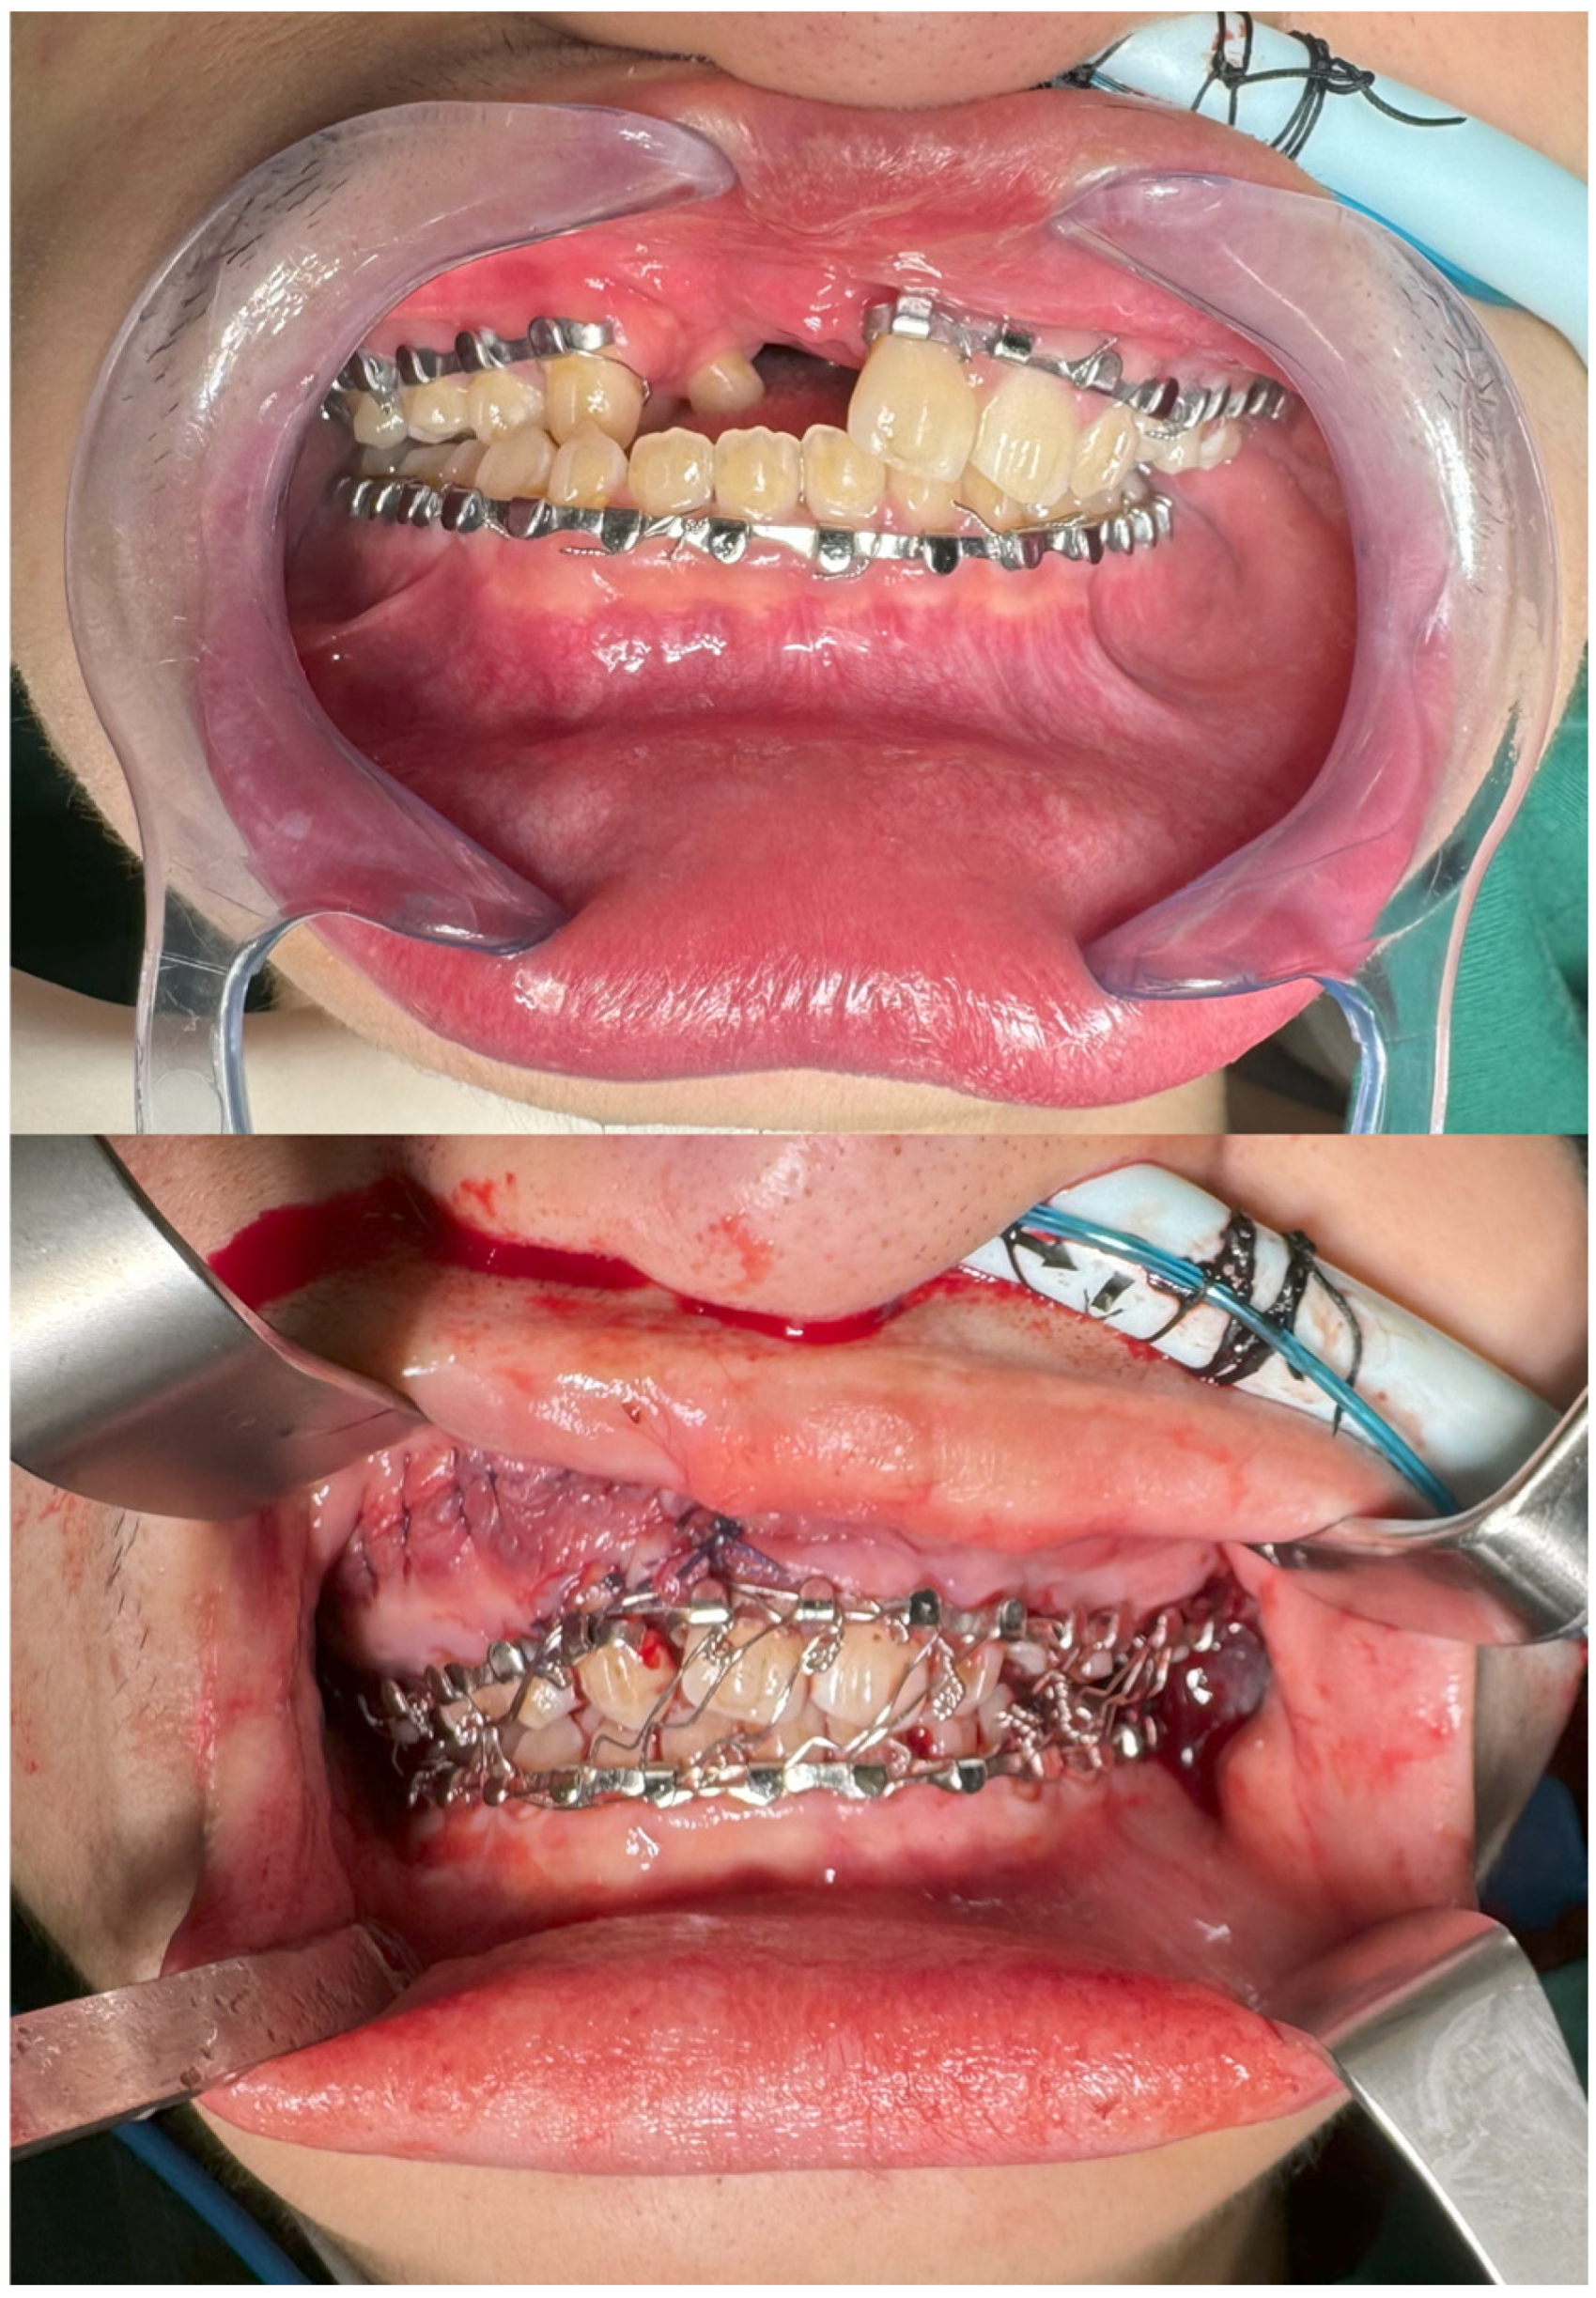

2. Materials and Methods

2.1. Preoperative Planning

2.2. Intra-Operative Navigation

3. Results